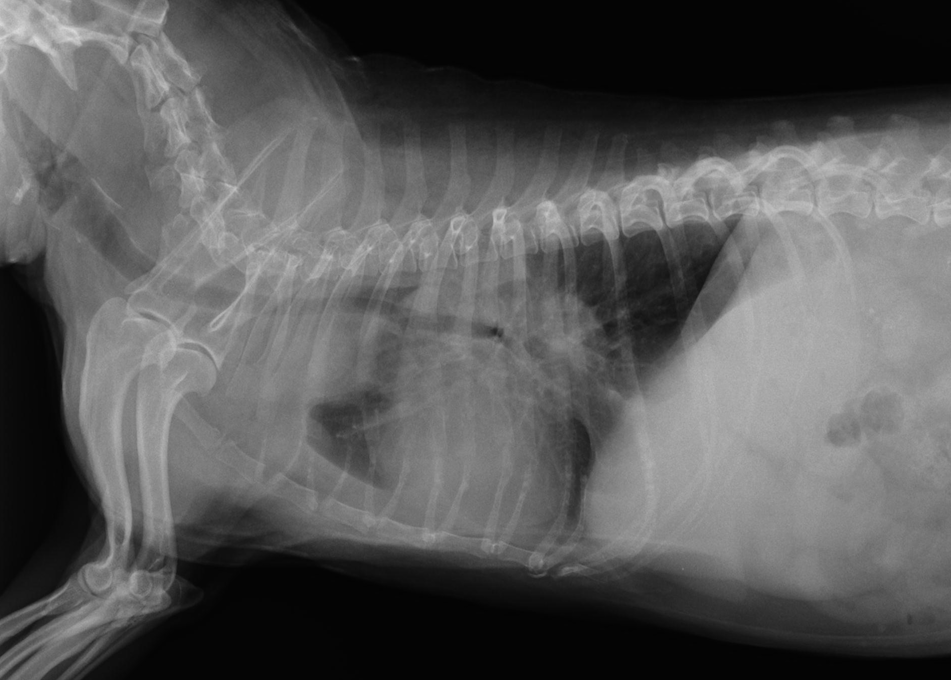

わんちゃんの巨大食道症。食道炎から二次的に起きる場合や、重症筋無力症の症状として発症する場合があります。合併症の誤嚥性肺炎の危険性があり、食後の立位の維持や少量ずつの食事などの看護が必要です。

重度な巨大食道と誤嚥性肺炎のわんちゃん

わんちゃんの巨大食道症。食道炎から二次的に起きる場合や、重症筋無力症の症状として発症する場合があります。合併症の誤嚥性肺炎の危険性があり、食後の立位の維持や少量ずつの食事などの看護が必要です。

重度な巨大食道と誤嚥性肺炎のわんちゃん